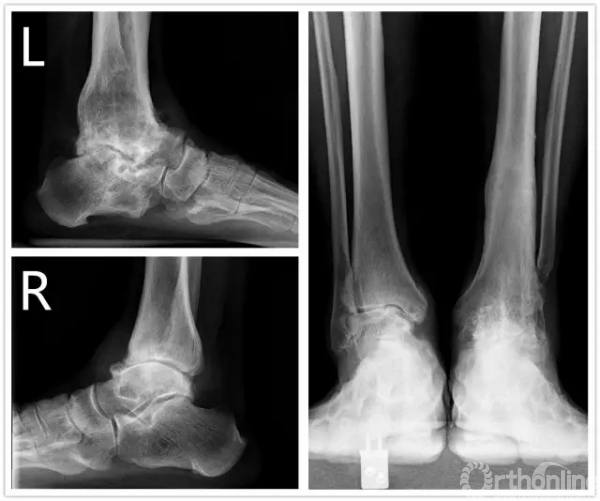

方老伯,今年67岁,2006年7月他因左侧踝关节严重骨关节炎到上海瑞金医院就诊,当时刘津浩副主任考虑其踝关节和距下关节都已经出现严重的骨关节炎,无法保留关节,于是对其进行了胫距跟双关节融合手术。手术后方老伯恢复良好,如期达到骨性融合。2年后,方老伯右侧踝关节开始出现肿胀疼痛,日夜反复发作,直到2010年2月,他无法忍受,再来医院就诊,拍片后发现他右侧踝关节也出现明显骨关节炎。此时正值瑞金医院足踝外科全面发展时期,足踝外科的新理念、新技术已经引入瑞金医院,当时学科带头人徐向阳主任认为该患者左侧踝关节已经行融合手术,右侧不适宜再行融合手术。于是徐主任主刀、刘津浩副主任和朱渊医师担任助手,顺利为方老伯进行了踝关节STAR假体置换术,手术后保持随访康复良好,又恢复了往常的劳作。